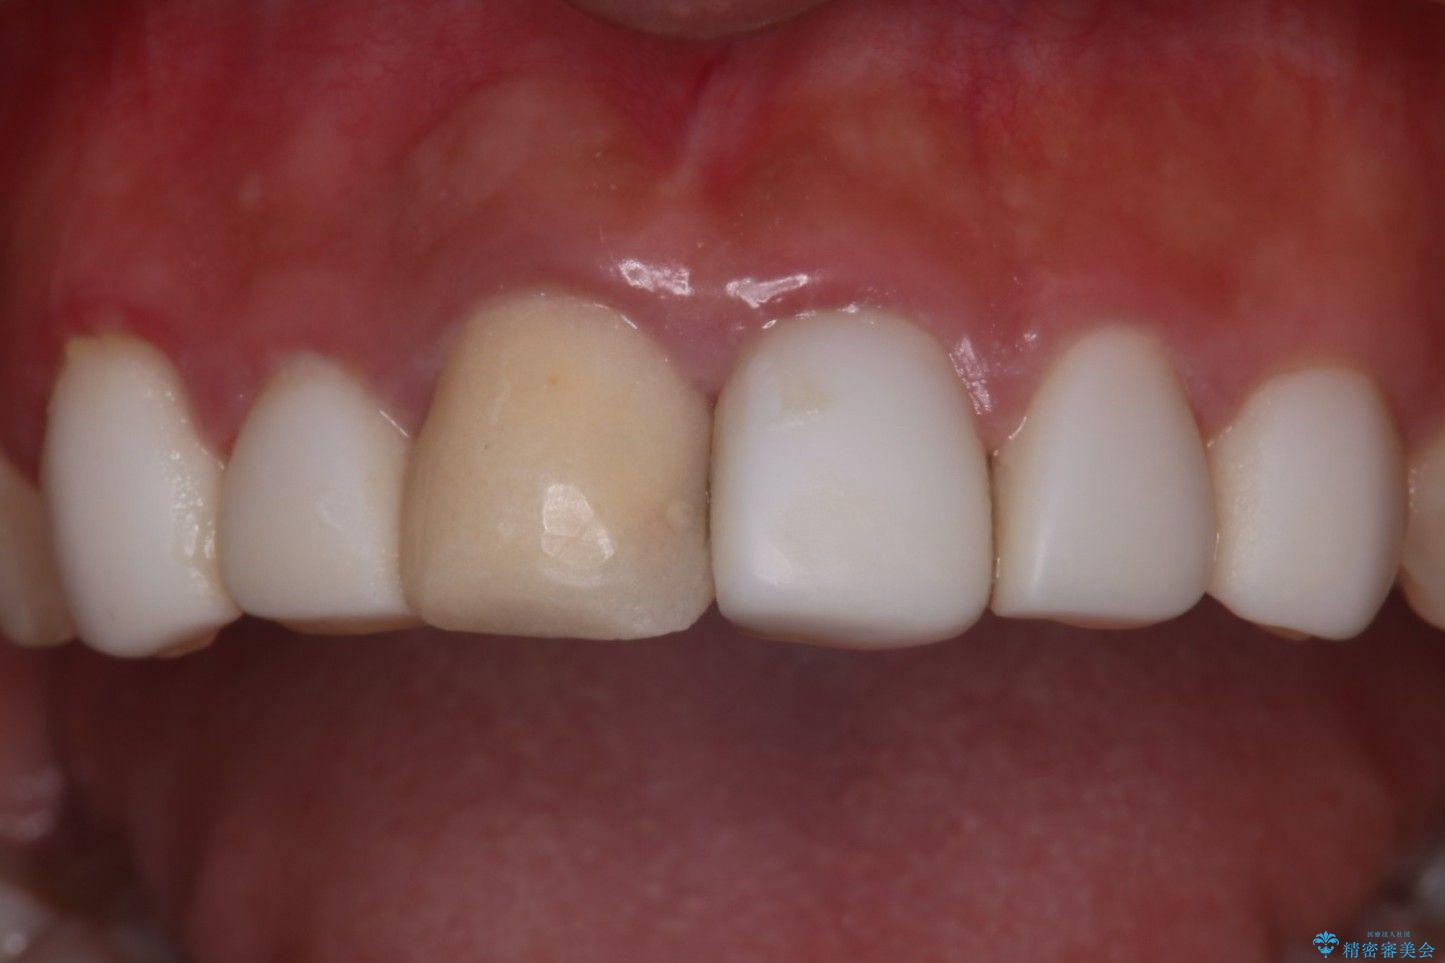

- 他院で治療した前歯の色が気になるということで来院された患者様です。前歯に色の差があり、レントゲンから内部にう蝕も見られたため、審美性に優れ、う蝕になりにくいオールセラミッククラウンで治療いたしました。

清掃性も上がったおかげで、歯肉の状態も良好に保てています。

色の調和もとれたので非常に満足いただけました。